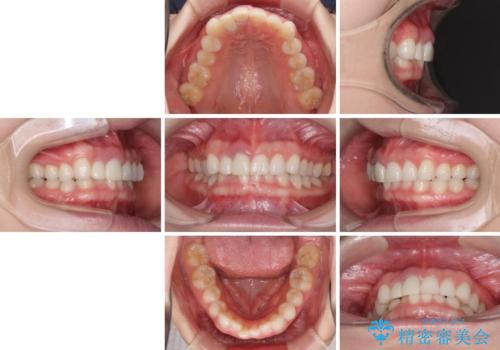

- 一度矯正治療を希望して始めたものの断念し、前歯をセラミッククラウンで治療した後に、やはり矯正でしっかり治したいとのことで来院された患者様です。

当初、前歯の歯列矯正を希望して銀座院に来院され、補助装置を装着するところまで進んだのですが断念してしまいました。

その後、他院で気になる前歯をセラミッククラウンで補綴治療をしたそうですが、やはり歯列を整えたいとのことで再度来院されました。

クラウンの状態は、根管治療の状態も含めて決して良い状態とは言えず、矯正治療後の根管治療と補綴治療の再治療を前提として、インビザラインによる矯正治療を行うこととしました。

治療前、下顎前歯はほとんど見えない咬み合わせでしたが、矯正治療によりディープバイトが改善されました。

矯正治療中に前歯2本のクラウンは外れてしまい、途中仮歯に替える必要があったので期間は掛かりましたが、歯列も整い、負担のかからない咬み合わせを達成することができました。